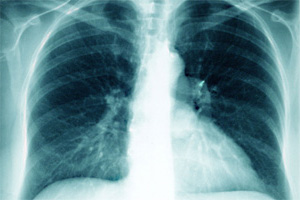

Wie beeinträchtigen Umweltfaktoren die Gesundheit? Welche molekularen und zellulären Mechanismen liegen diesen Störungen zugrunde und welche Rolle spielt dabei die genetische Disposition? Welche neuen Strategien der Prävention und Therapie lassen sich daraus ableiten? Dies sind Leitfragen dieses Forschungsprogramms. Im Fokus stehen häufig auftretende Krankheiten wie Entzündungen des Atemtraktes, Allergien und Krebs, an deren Entstehung Umweltschadstoffe wie partikelförmige Luftverunreinigungen (Aerosole), Chemikalien oder ionisierende Strahlen wesentlich beteiligt sind.